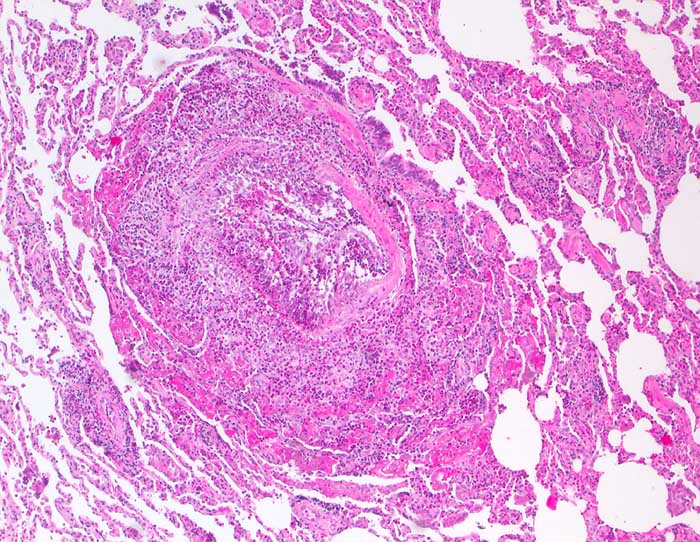

Churg Strauss Vaskulitis

Destruktive eosinophile Vaskulitis einer kleinen Arterie.

Der morphologische Befund ist klassisch für ein Churg-Strauss-Syndrom und passt auch zu der Anamnese eines mehrjährigen Asthmas mit aktueller Bluteosinophilie und IgE-Erhöhung. Der Befund könnte im Zusammenhang stehen mit einer ca. seit drei Monaten bestehenden Therapie mit Leukotrien-Rezeptorantagonisten, welche nach Berichten aus der Literatur ein Churg-Strauss-Syndrom möglicherweise demarkieren können.